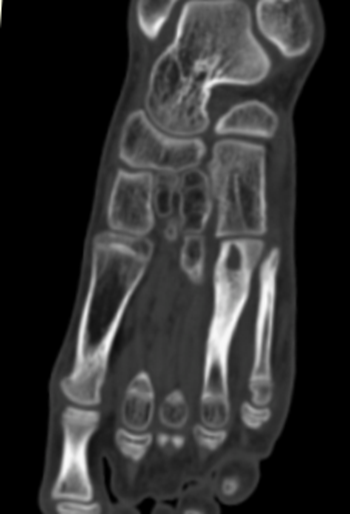

Спицевой канал был шире в области кортикальной пластинки. Плотность стенок спицевого канала увеличивалась до 480 [420;620] HU (медиана) (рис. 4, а). При локализации СО в дистальной трети большеберцовой кости и длительном течении заболевания (больше года) изменения в данной области проявлялись участками деструкции, нарушением структуры кости, появлением зон разрежения и склероза. Во всех случаях воспалительный и деструктивный процесс распространялся на кости стопы, сопровождаясь дефектами, изменением структуры с нарушением органотипического строения костей, зонами резорбции (рис. 4, б, в).

-4

В области диафиза воспалительные изменения — более ограниченные, особенно в тех случаях, когда были приняты своевременные меры для ликвидации очага инфекции (раннее хирургическое дренирование и адекватная антибактериальная терапия). Эти данные получены при анализе историй болезни пациентов, в которых отмечено быстрое купирование воспалительного процесса при применении комплексного лечения в первые одну-две недели от начала заболевания. В случаях длительного течения заболевания (обычно более трех-четырех недель) формировались широкие спицевые каналы и секвестры.